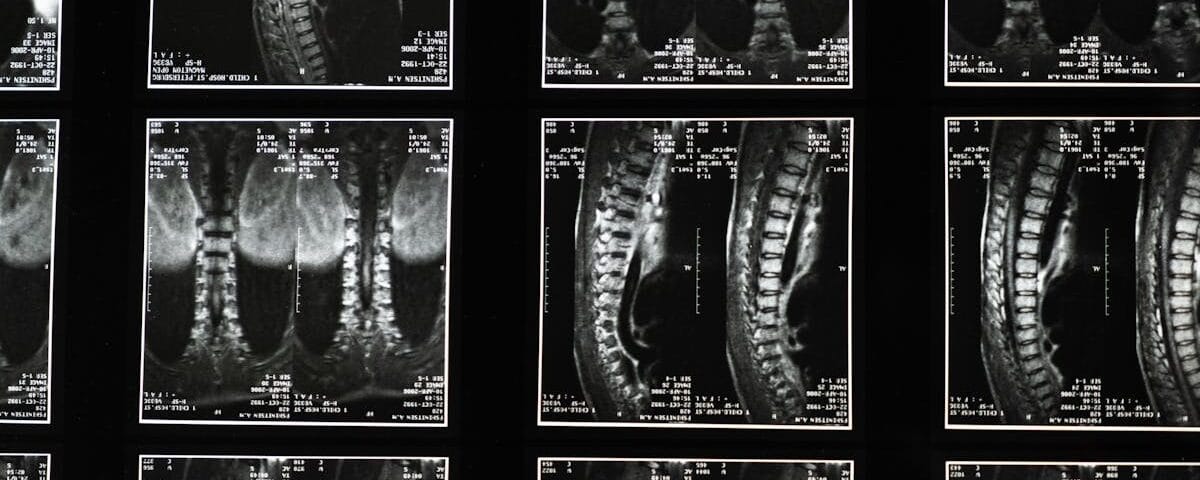

Before starting a decompression treatment, it is crucial to obtain an accurate diagnosis of the underlying condition. This includes thorough evaluations such as imaging examinations to identify the exact location of the problem. Once the diagnosis is established, the treatment can be tailored to effectively target sciatic pain.

Un examen clinique approfondi et des imageries comme une IRM ou une radiographie sont souvent nécessaires.

Une consultation clinique et des examens d’imagerie comme l’IRM sont nécessaires pour déterminer l’éligibilité.